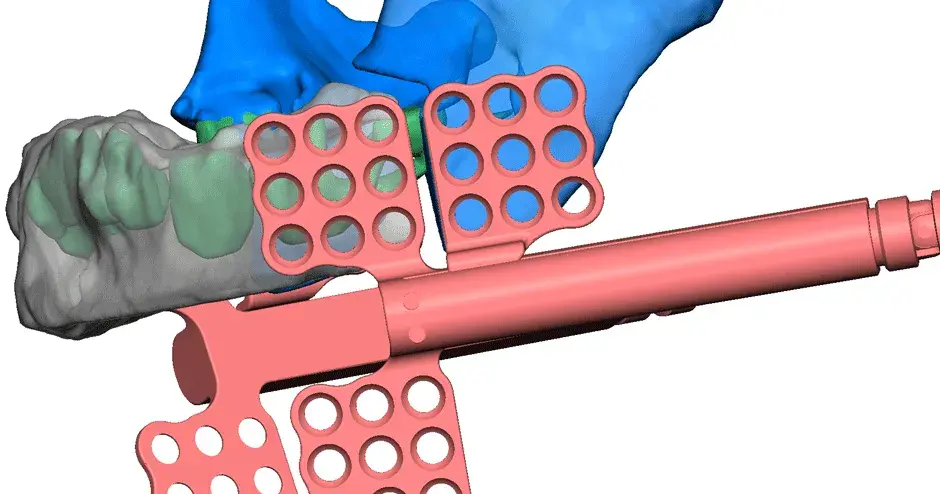

3D Systems' VSP® surgical planning solutions for craniomaxillofacial (CMF) applications received FDA clearance as a service-based approach to personalized surgery over 10 years ago.

3D Systems and Stryker Corporation have partnered to provide surgeons with best-in-class products and services for craniomaxillofacial surgeries. As a leader in personalized healthcare solutions, 3D Systems has planned and delivered devices for more than 140,000 patient-specific cases. The Stryker Craniomaxillofacial business specializes in providing patient-specific options and innovative solutions that help drive efficiencies in surgical suites. The combination of Stryker’s specialized team and advanced implants with 3D Systems' cutting-edge 3D printing technologies and expert consulting services positions both companies to provide a superior level of service to healthcare professionals who use these revolutionary solutions.